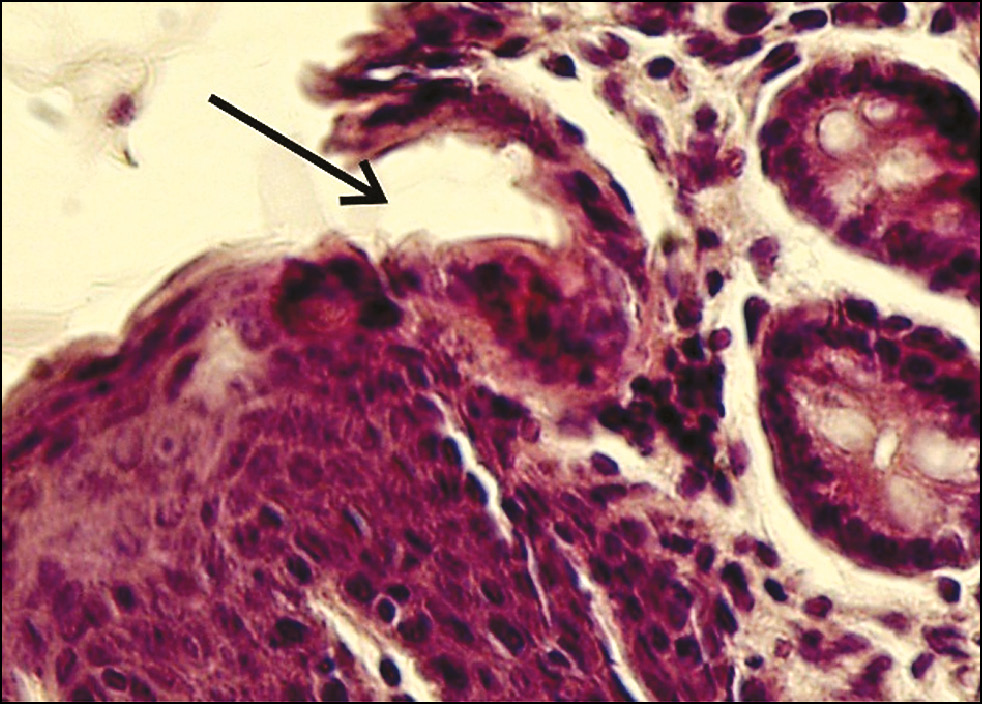

Рис. 5. Эмбрион крысы на 18-е сутки развития — зона взаимодействия эпителиев кожной и кишечной части аноректального канала (указана стрелкой). Окраска гематоксилином и эозином, увеличение ×400.

Fig. 5. Epithelial interaction zone (indicated by an arrow) between the cutaneous and intestinal parts of the anorectal canal in an 18-day-old rat embryo. Hematoxylin and eosin staining, ×400 magnification.

У эмбрионов крысы на 15-е сутки развития уже сформирован аноректальный канал и возникает контакт кожного и кишечного эпителиев. В АРК строение эпителия изменяется при переходе из одной части канала в другую, при этом отсутствует эпителий, сходный с таковым в мочевой части клоаки у клоачных животных. На его месте располагается короткий участок, морфологическая картина которого свидетельствует о дезорганизации многослойного эпителиального пласта (рис. 4). Кариометрические показатели эпителиоцитов кожной и кишечной частей АРК у эмбрионов крысы на 15 сутки развития представлены в табл. 1. На 18-е сутки развития в области контакта кожного и кишечного эпителиев обнаруживается скопление округлых гиперхромных клеток (рис. 5).